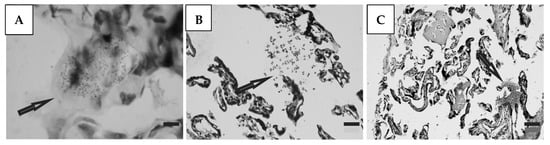

3.5. Histological Studies

Histological preparations of placental tissue sections representative of non-transmitter and transmitter mothers are shown in Figure 2 and Figure 3. Different forms of the parasite were detected through the microscopic observation of chorionic villous human placenta from these mothers. Amastigote nests were observed in preparations from non-transmitter (Figure 2A,B) and transmitter (Figure 3A) mothers, while released parasites were found in placentas from non-transmitter (Figure 2C) and transmitter (Figure 3B,C) mothers.

Figure 3.

Histological section of the placenta from a transmitter mother. Arrows point to (A) amastigote nest; and (B,C) released parasites (H&E). Scale bar: 25 μm.